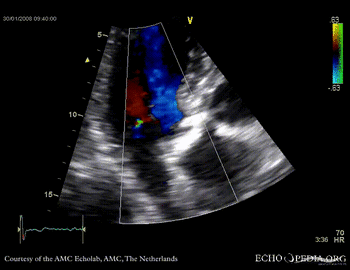

Aortic valve stenosis

AoS3